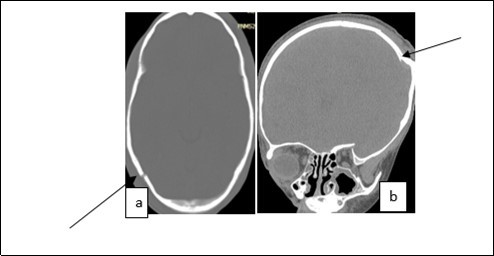

From the point of view of care, two (n=2) (10.52%) children received medical treatment compared to 17 (89.48%) children who received medical-surgical treatment. Neurosurgical treatment consisted of evacuation of the extra dural hematoma. This involved making a skin incision, trepanation (Figure 3 a), a preserved cranial bone flap, evacuation of the extra-dural haematoma (Figure 3 b), haemostasis either of the bone using bone wax or venous or arterial haemostasis by bipolar coagulation as appropriate, suspension of the dura mater (Figure 3 c), replacement of the bone flap (Figure 3 d) and finally suturing of the scalp in two planes. Figure 1, Figure 2, Figure 3.

Figure 2.Image of a brain CT scan without contrast agent injection in a bone window, axial section showing a right parieto-occipital fracture (a), coronal section showing a left parietal skull depressed fracture (b)

Image of a brain CT scan without contrast agent injection in a bone  window, axial section showing a right parieto-occipital fracture (a), coronal     section showing a left parietal skull depressed fracture (b)